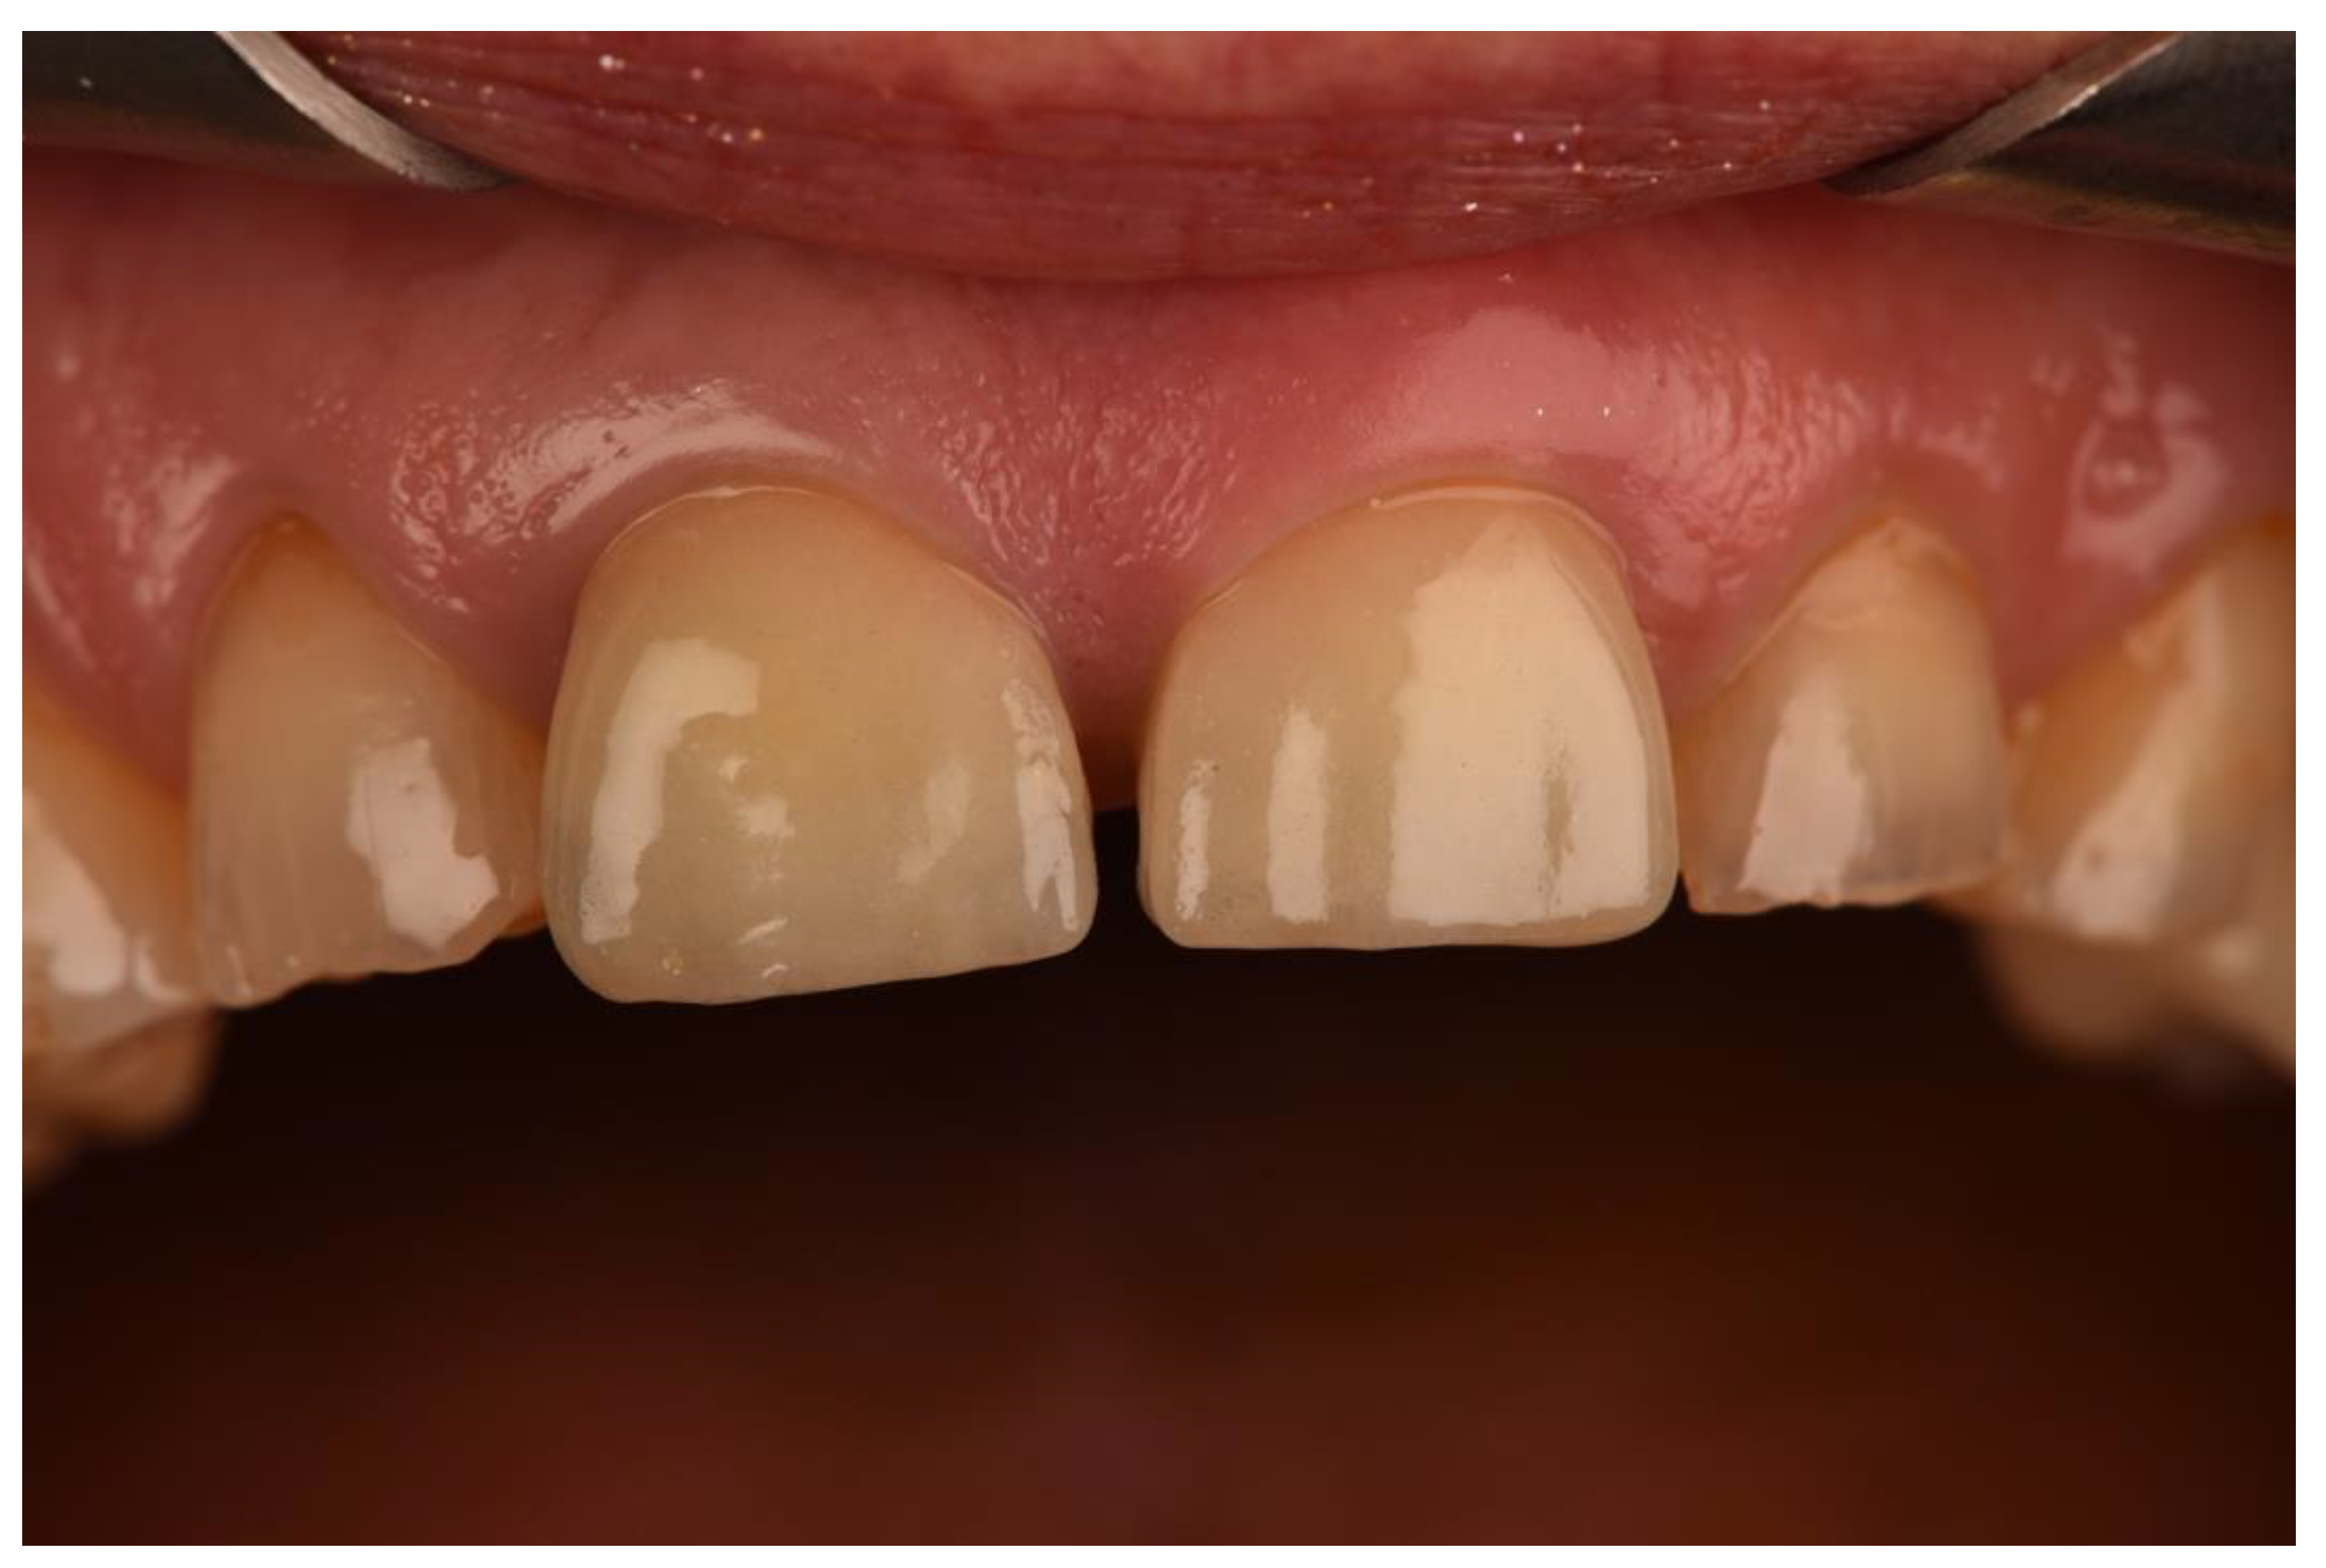

- Vilor-Fernández, V.; García-de-la-Fuente, A.M.; Marichalar-Mendia, X.; Estefanía-Fresco, R.; Aguirre-Zorzano, L.A. Single tooth restoration in the maxillary esthetic zone using a one-piece ceramic implant with 1 year of follow-up: Case series. Int. J. Implant. Dent. 2021, 7, 26. [Google Scholar] [CrossRef] [PubMed]